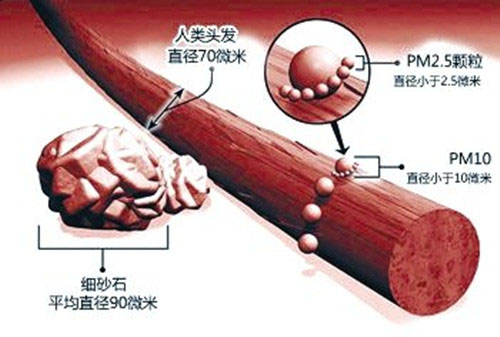

PM2.5是什麽

PM是英文Particulatematter颗粒物的缩写,2.5则表示这种颗粒物的直径。颗粒物一般分为两类:PM2.5和PM10。 PM2.5是指直径小於或等於2.5微米的颗粒物,相当於头发丝直径的1/20,已到达肺泡的临界值。 PM2.5以下的细微颗粒物,人体的鼻腔丶咽喉已经挡不住,它们可以一路下行,进入细支气管丶肺泡,再通过肺泡壁进入毛细血管,再进入整个血液循环系统。对人体的呼吸系统和心血管系统造成伤害。

PM10是直径小於或等於10微米的颗粒物,体积是的PM2.5的64倍,咽喉是PM10的终点站,咽喉表面分泌的黏液会粘住它们,可以通过吐痰排出,所以对人体的危害并不大。